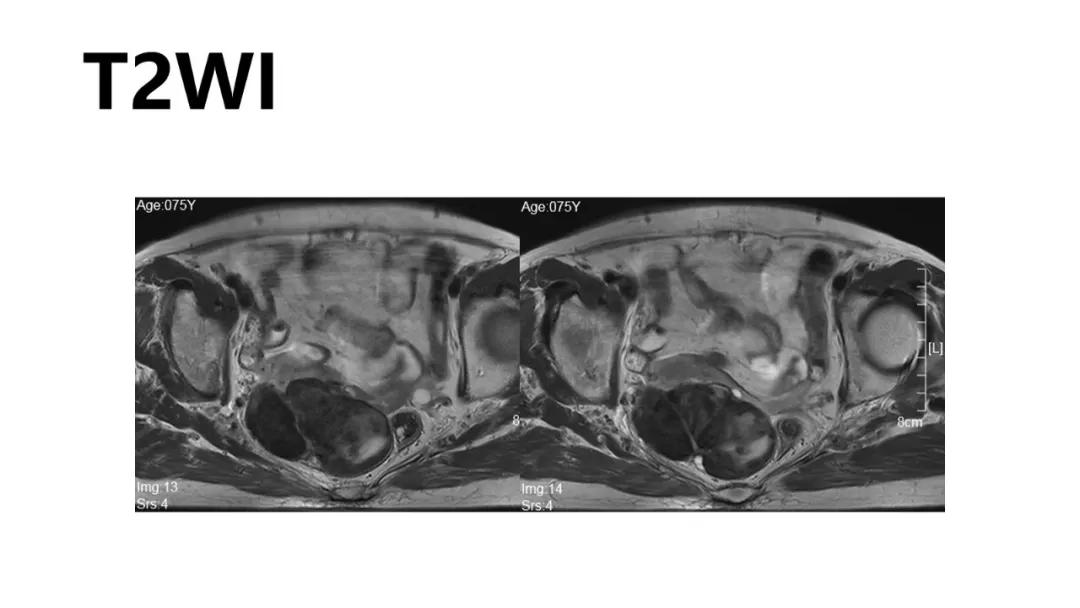

病例10

女,39 岁,体检发现盆腔肿块1月余

CA125:51U/ml

病理:左侧卵巢卵泡膜-纤维瘤